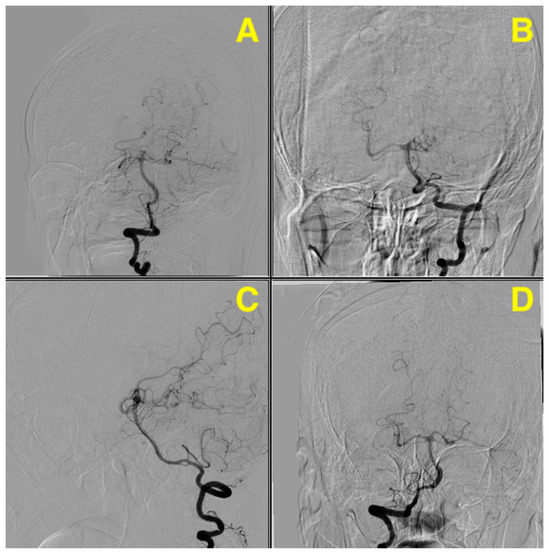

The 3D angiographic reconstruction (Figure 2) revealed the precise dimensions of the aneurysm located on the superior cerebellar artery. The aneurysm measured 4.69 mm in length and 3.55 mm in width, with a neck diameter of 2.06 mm. These measurements are particularly important when evaluating treatment options, as the size and shape of the aneurysm influence the feasibility of endovascular procedures such as coiling, where smaller neck sizes are generally more amenable. The dome-to-neck ratio, an important factor in deciding between endovascular and surgical intervention, was clearly visible, further aiding in the planning for optimal treatment. The accurate visualization of these dimensions, along with the aneurysm’s anatomical relationship to adjacent vessels, was critical in guiding the neurosurgical team’s decision-making process.

Figure 2. Pre-op 3D angiographic reconstruction. (A) offers an overview of the posterior circulation anatomy, emphasizing the aneurysm’s location and its spatial relationship to the basilar artery bifurcation. (B) provides precise measurements of the aneurysm, with a dome size of 4.69 mm, a width of 3.55 mm, and a neck diameter of 2.06 mm. The high-resolution 3D imaging highlights the aneurysm’s morphology, including its lateral and posterior orientation, and the vascular structures surrounding it.